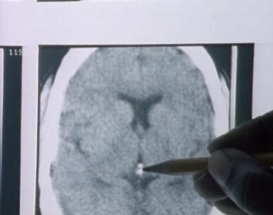

Neuropsychiatrist Dr. Roger Mallory, of the Haitian Medical Society, conducted a scan of zombiefied Wilfred’s brain. Although the results were not as definite as had been hoped for, he and his colleagues found brain damage consistent with oxygen starvation. It would seem that zobiefication is nothing more then a skillful act of poisoning. The bodily functions of the poisoned person suspend so that he appears dead. After he is buried alive, lack of oxygen damages the brain. If the person is unburied before he really dies from suffocation, he will appear as a soulless creature (‘zombie’) as he has lost what makes him human: the thinking process of the brain666We must observe that Davis’ link between zombiefication and TTX has been viewed with skepticism. Unfortunately, there has been no direct proof along this direction and, therefore, Davis’ claim remains an intriguing hypothesis. There are only a few scientific studies on zombies (at least to the best of our knowledge). One interesting study is that of the anthropologist Rolland Littlewood and Dr Chavannes Douyon [Littlewood & Douyon 1997] who looked at three alleged zombie cases. In all cases they were able to find medical explanations..